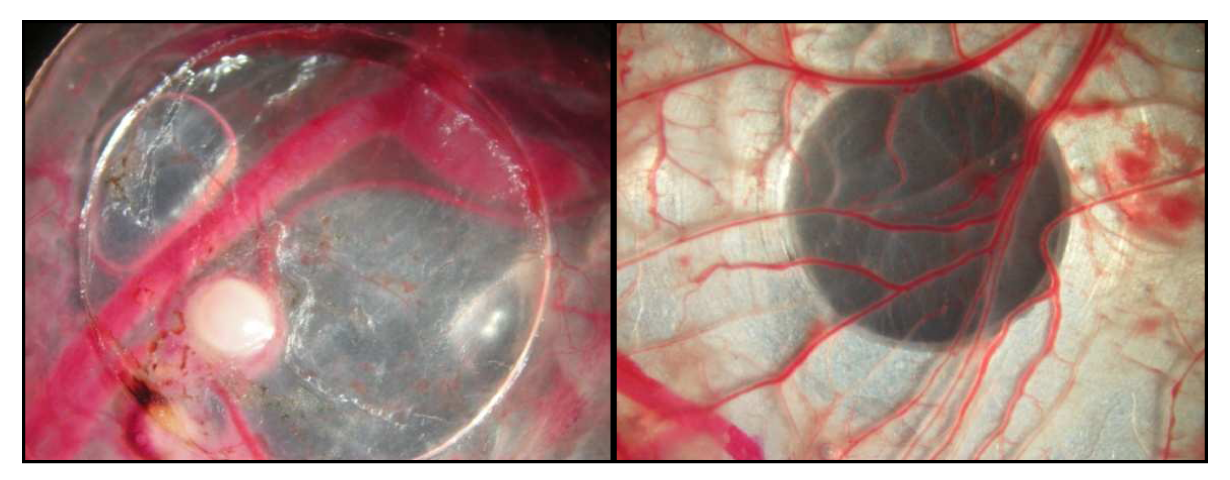

The same ratio was observed for sample 5. Nevertheless, fluorine distribution has been determined (Figure 3) in accordance with capillaries identification with iron measurements. In sample 5 (Figure 3-B, Table 2), fluorine amount decreased from the CAM tissue (330 ± 60 μg/g) to the successive tumor sections (from 300 ± 30 μg/g for S2 close to CAM to 130 ± 20 μg/g for S4). The low accumulation in tumor tissue is most probably due to the fact that poorly vascularized tumors were injected (Figure 5)

Figure 5. Tumor tissue with vascularisation on ring (left), CAM on aluminium target (right).